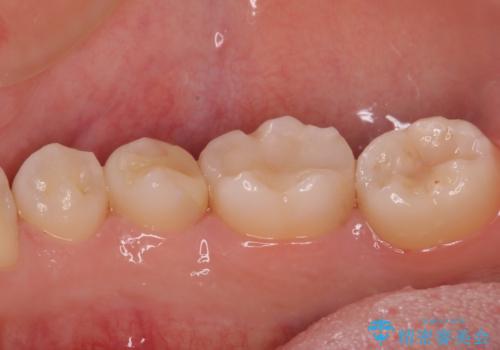

レントゲン写真などから、速やかに処置を行うべき歯が2歯あったため、それぞれセラミックインレーとPGAインレー(ゴールドインレー)にて修復治療を行うこととしました。

どちらの歯も痛みなどの症状はなく、治療後も異常所見なく経過をたどっています。

上顎大臼歯は向かい合った人から見えることはほとんどないため、切削量が少なく、適合の良いゴールドインレーが大変おすすめとなります。